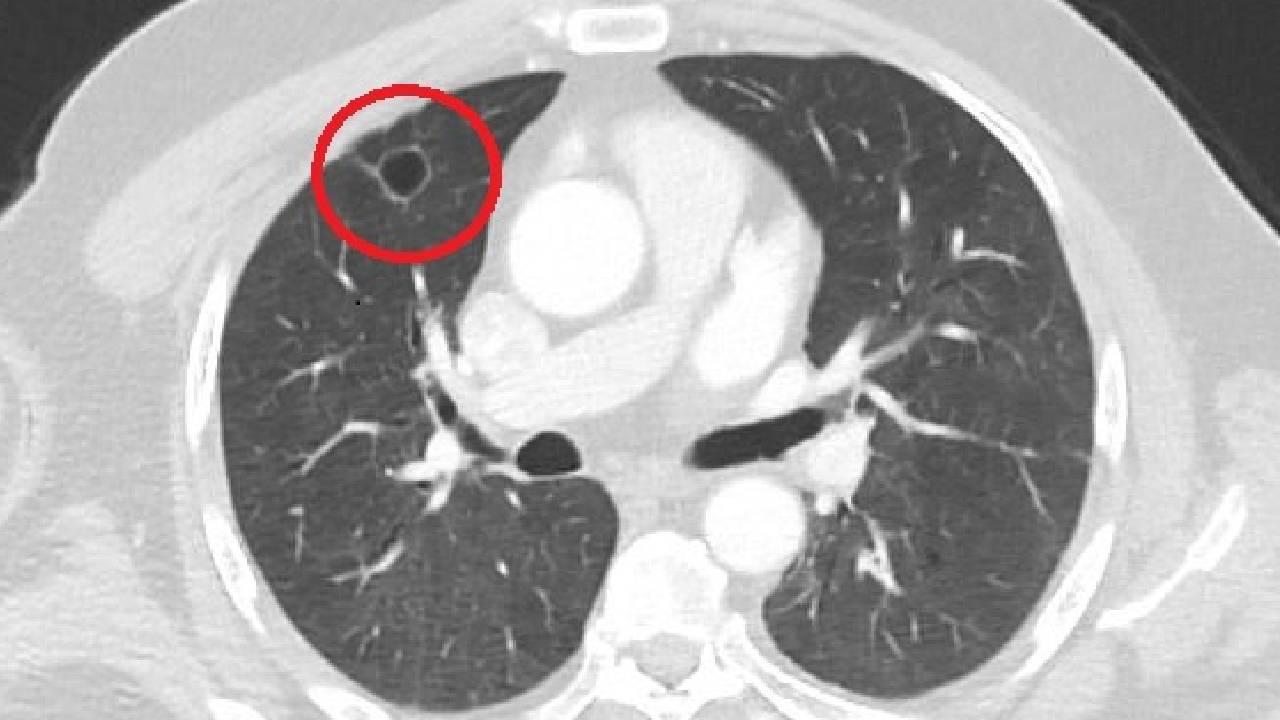

Akciğer sağlığı, koronavirüs tehdidi altında.. Uzmanlar, salgın nedeniyle akciğer hastalıklarından biri olan Tüberküloz yani bilinen adıyla verem teşhisinin azaldığını ancak ölümlerin devam ettiğini vurguluyor.